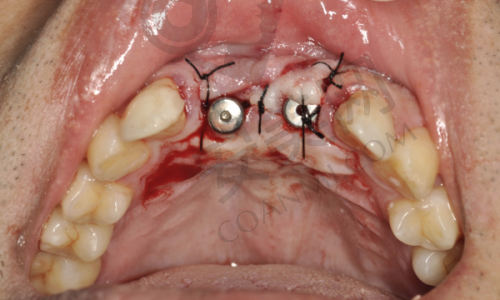

终于到了种植牙手术的那天,我心里还是有点紧张的。医生给我打了局部麻醉,在麻醉生效后才开始手术。整个手术过程中,我并没有感觉到明显的疼痛,只是能感觉到医生在操作。医生的技术非常娴熟,动作特别轻柔,每一个步骤都特别精细。手术持续了大概一个多小时,结束后,医生详细地跟我交代了术后的注意事项,比如要注意口腔卫生、避免吃辛辣刺激的食物等。术后,麻醉药效过了之后,确实有一些轻微的疼痛和肿胀,但都在可以忍受的范围内。医生给我开了一些消炎药和止痛药,按照医嘱服用后,疼痛和肿胀特别快就缓解了。

宿州康桥口腔医院的种植牙技术有特别多特色之处。首先,他们采用的是精良的种植系统,这些种植体的材质非常好,生物相容性高,能够与牙槽骨更好地结合,提高种植牙的成功几率。其次,医院拥有专精的医生团队,他们都有丰富的临床经验,能够根据患者的具体情况制定更适合的种植方案。而且,医院还引进了精良的数字化种植技术,通过计算机模拟种植过程,能够更精细地确定种植体的位置和角度,减少手术创伤,缩短手术时间。另外,医院的服务也非常贴心,从术前的询问、检查,到术中的治疗,再到术后的回访和维护,都有专人跟进,让患者感受到全方面的关怀。